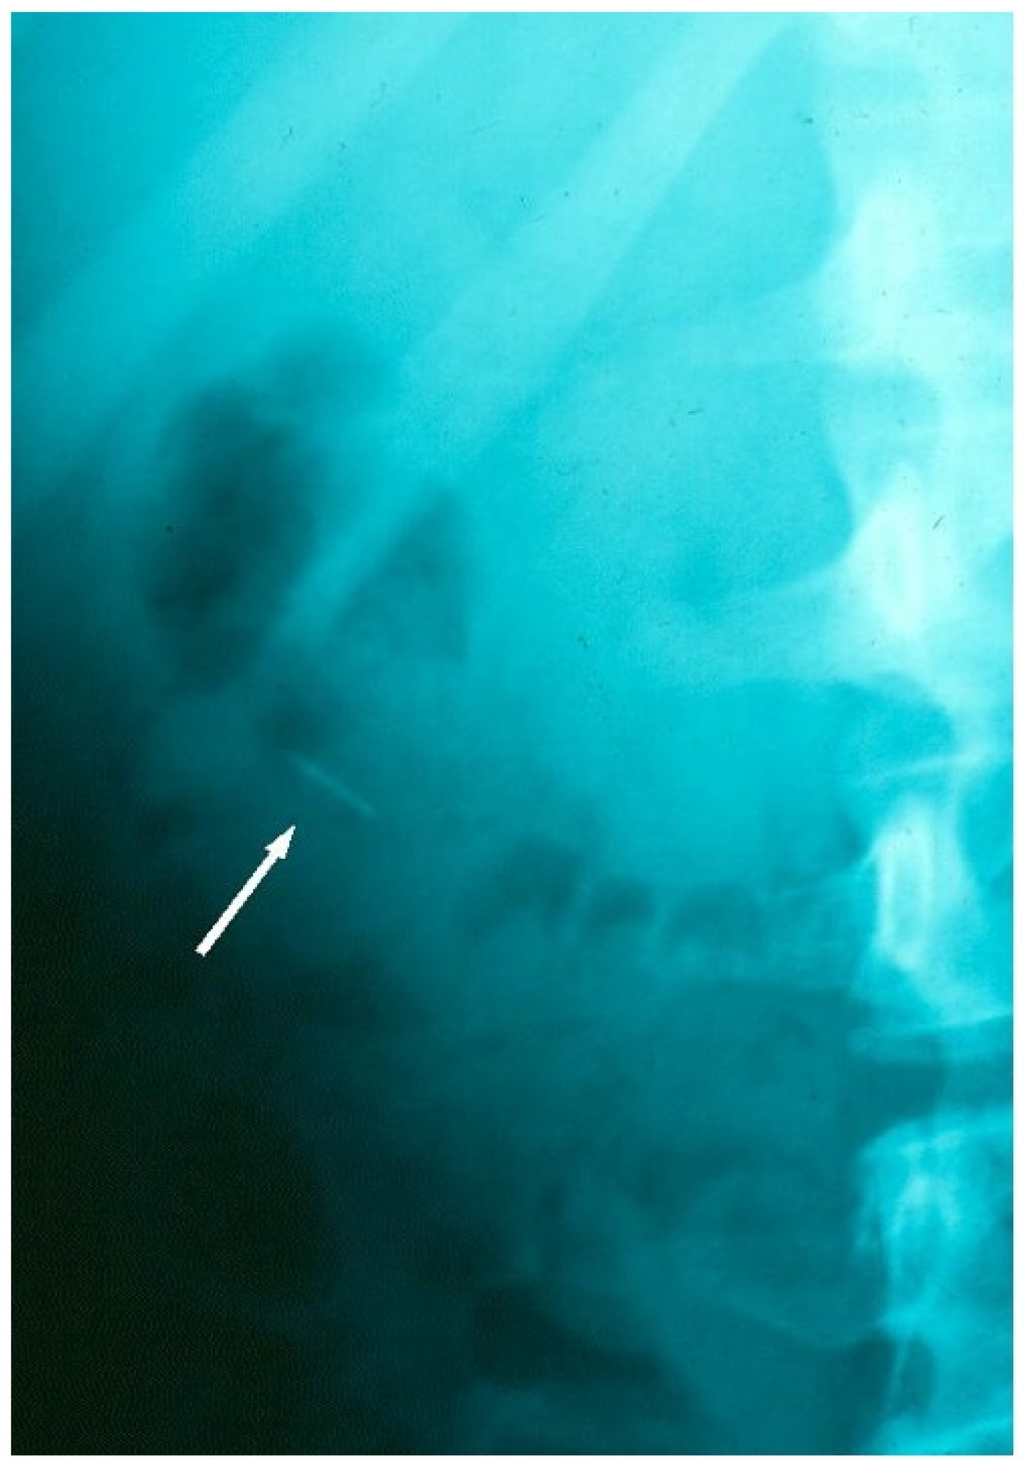

Figure 2.

Radiographic tracking view, confirming the archwire fragment location in the colon, during its safe passage through the GIT.